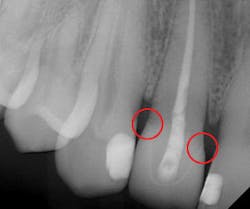

The majority of patients have two primary concerns with any indirect restorative procedure: (1) is it worth the sizable financial investment, and (2) how comfortable or painful will it be? With unadjusted proximal contacts, this procedure has failed on both counts. Based on the 2013 Survey of Dental Fees from the American Dental Association,1 the patient has spent roughly between $800 and $1,400 on a restoration that is short-lived, uncomfortable, and necessitates further treatment and discomfort (figure 1).

Figure 1: Incomplete marginal seating due to overly tight proximal contacts.